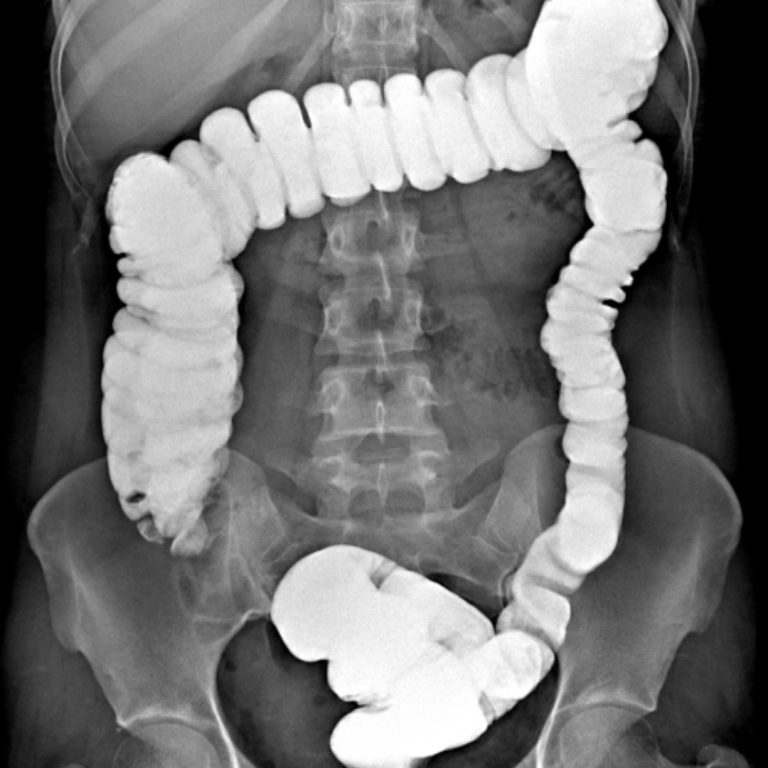

KOLON GRAFİLERİ

İki çeşit baryumlu kolon incelemesi vardır; tek kontrast ve çift kontrast. Kolon kanseri taramasında genellikle çift kontrastlı kolon tetkiki kullanılır.

- Tek Kontrastlı Kolon grafisi

Teknisyen makata bir tüp yerleştirir ve tüpün ucu baryum solüsyonunun olduğu torbaya bağlanır. Verilen baryum yavaşça kolonu sıvar. Bu şekilde kolon görünür hale gelir. Kolon baryum ile doldukça, dışkılama hissi duyulabilir. Baryum vermek için rektuma yerleştirilen tüpün ucunda küçük bir balon vardır. Tüp yerleştirildikten sonra baryum kaçışını engellemek için bu balon şişirilir. Tetkik esnasında masa üzerinde farklı yönlere dönülmesi istenebilir. Böylece verilen baryum tüm kolon segmentlerini doldurur ve kolonun farklı açılardan izlenmesine olanak sağlar. Filmler çekilirken nefesin tutulması istenir.

2- Çift Kontrastlı Kolon grafisi

Bu işlemin tek kontrastlı tetkikten en önemli farkı, kolonun hava ile doldurulmasıdır. Böylece daha kaliteli görüntü elde edilir. Polip gibi daha küçük lezyonlar rahatlıkla seçilebilir. Kolon tetkiki 20-30 dakikada tamamlanmakla birlikte, nadir durumlarda 45 dakikaya kadar çıkabilir. Bu tetkik karında hafif kramplara neden olabilir. Tetkikin bitimi ile şikâyetler sonlanır. Tetkik bitince rektuma yerleştirilen tüp çıkarılır ve kolonun boşaltılması istenir. Tetkiki takip eden birkaç gün dışkı, içeride kalan baryuma bağlı olarak beyaz, gri veya pembe görünümde olabilir. Geride kalan baryum kabızlığa neden olabileceğinden bol miktarda su içilmesi tavsiye olunur.

Rektal yoldan verilen kontrast madde takıntısız çekuma ulaşmış olup ilioçekal bileşke serbesttir. Apendiks vizüalize olmuştur ve normal görünümdedir. Rektum posterior konturu muntazamdır. Presakral mesafe açıktır. Kolon boyunca belirgin haustrasyon artışı mevcuttur. Sigmoid kolon hafif elonge görünümdedir. Kolon lümeninde doluş defekti lehine bulgu saptanmamıştır. Evakuasyon fazında sağ kolon ve hafif sigmoid kolon içinde remnant kontrast madde kalmıştır. Diğer segmentlerdeki kontrast maddenin bulunmaması mukozanın ödemli olabileceğini düşündürmektedir. Çift kontrastlı grafiler ve sağ kolondaki kontrast maddesinin fragmane olduğu dikkati çekmektedir. Bulgular irritable kolonla uyumlu bulunmuştur.